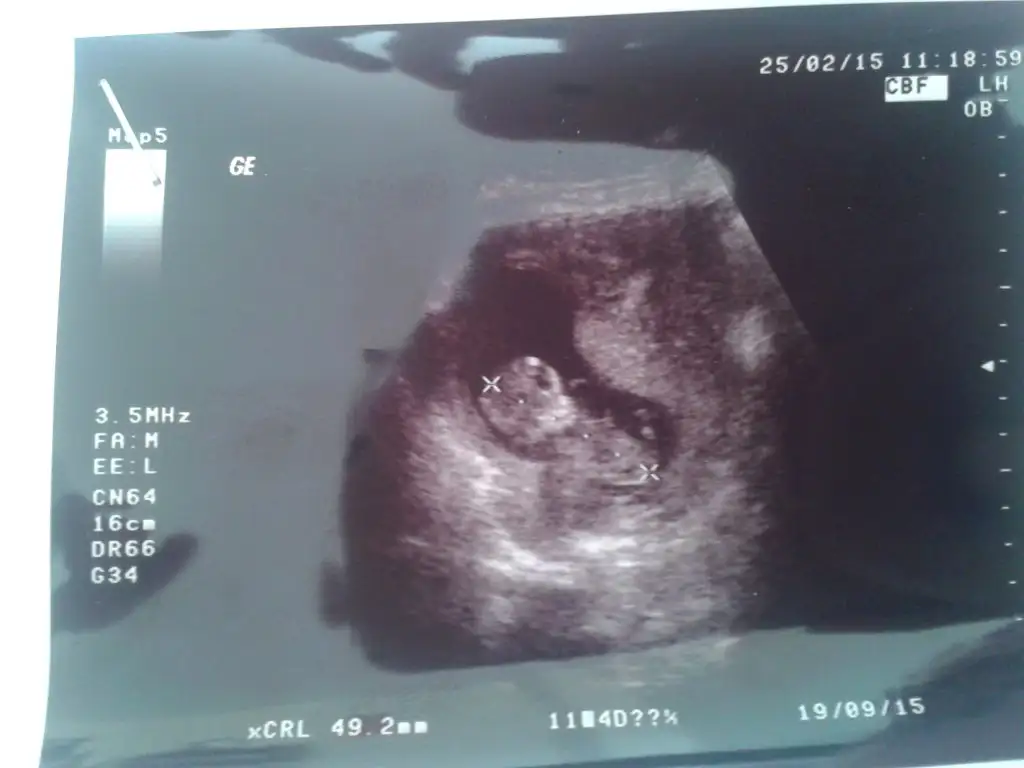

arkadaslar benimn bebisimede tahmın yapabilirmisiniz rica etsem :/

• 20150225_130534.webp

20150225_130534.webp

19,7 KB · Görüntüleme: 124